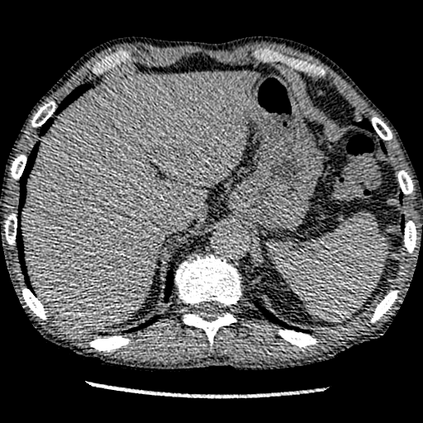

We propose a novel continual self-supervised learning (CSSL) framework for simultaneously learning diverse features from multi-window-obtained chest computed tomography (CT) images and ensuring data privacy. Achieving a robust and highly generalizable model in medical image diagnosis is challenging, mainly because of issues, such as the scarcity of large-scale, accurately annotated datasets and domain shifts inherent to dynamic healthcare environments. Specifically, in chest CT, these domain shifts often arise from differences in window settings, which are optimized for distinct clinical purposes. Previous CSSL frameworks often mitigated domain shift by reusing past data, a typically impractical approach owing to privacy constraints. Our approach addresses these challenges by effectively capturing the relationship between previously learned knowledge and new information across different training stages through continual pretraining on unlabeled images. Specifically, by incorporating a latent replay-based mechanism into CSSL, our method mitigates catastrophic forgetting due to domain shifts during continual pretraining while ensuring data privacy. Additionally, we introduce a feature distillation technique that integrates Wasserstein distance-based knowledge distillation (WKD) and batch-knowledge ensemble (BKE), enhancing the ability of the model to learn meaningful, domain-shift-robust representations. Finally, we validate our approach using chest CT images obtained across two different window settings, demonstrating superior performance compared with other approaches.